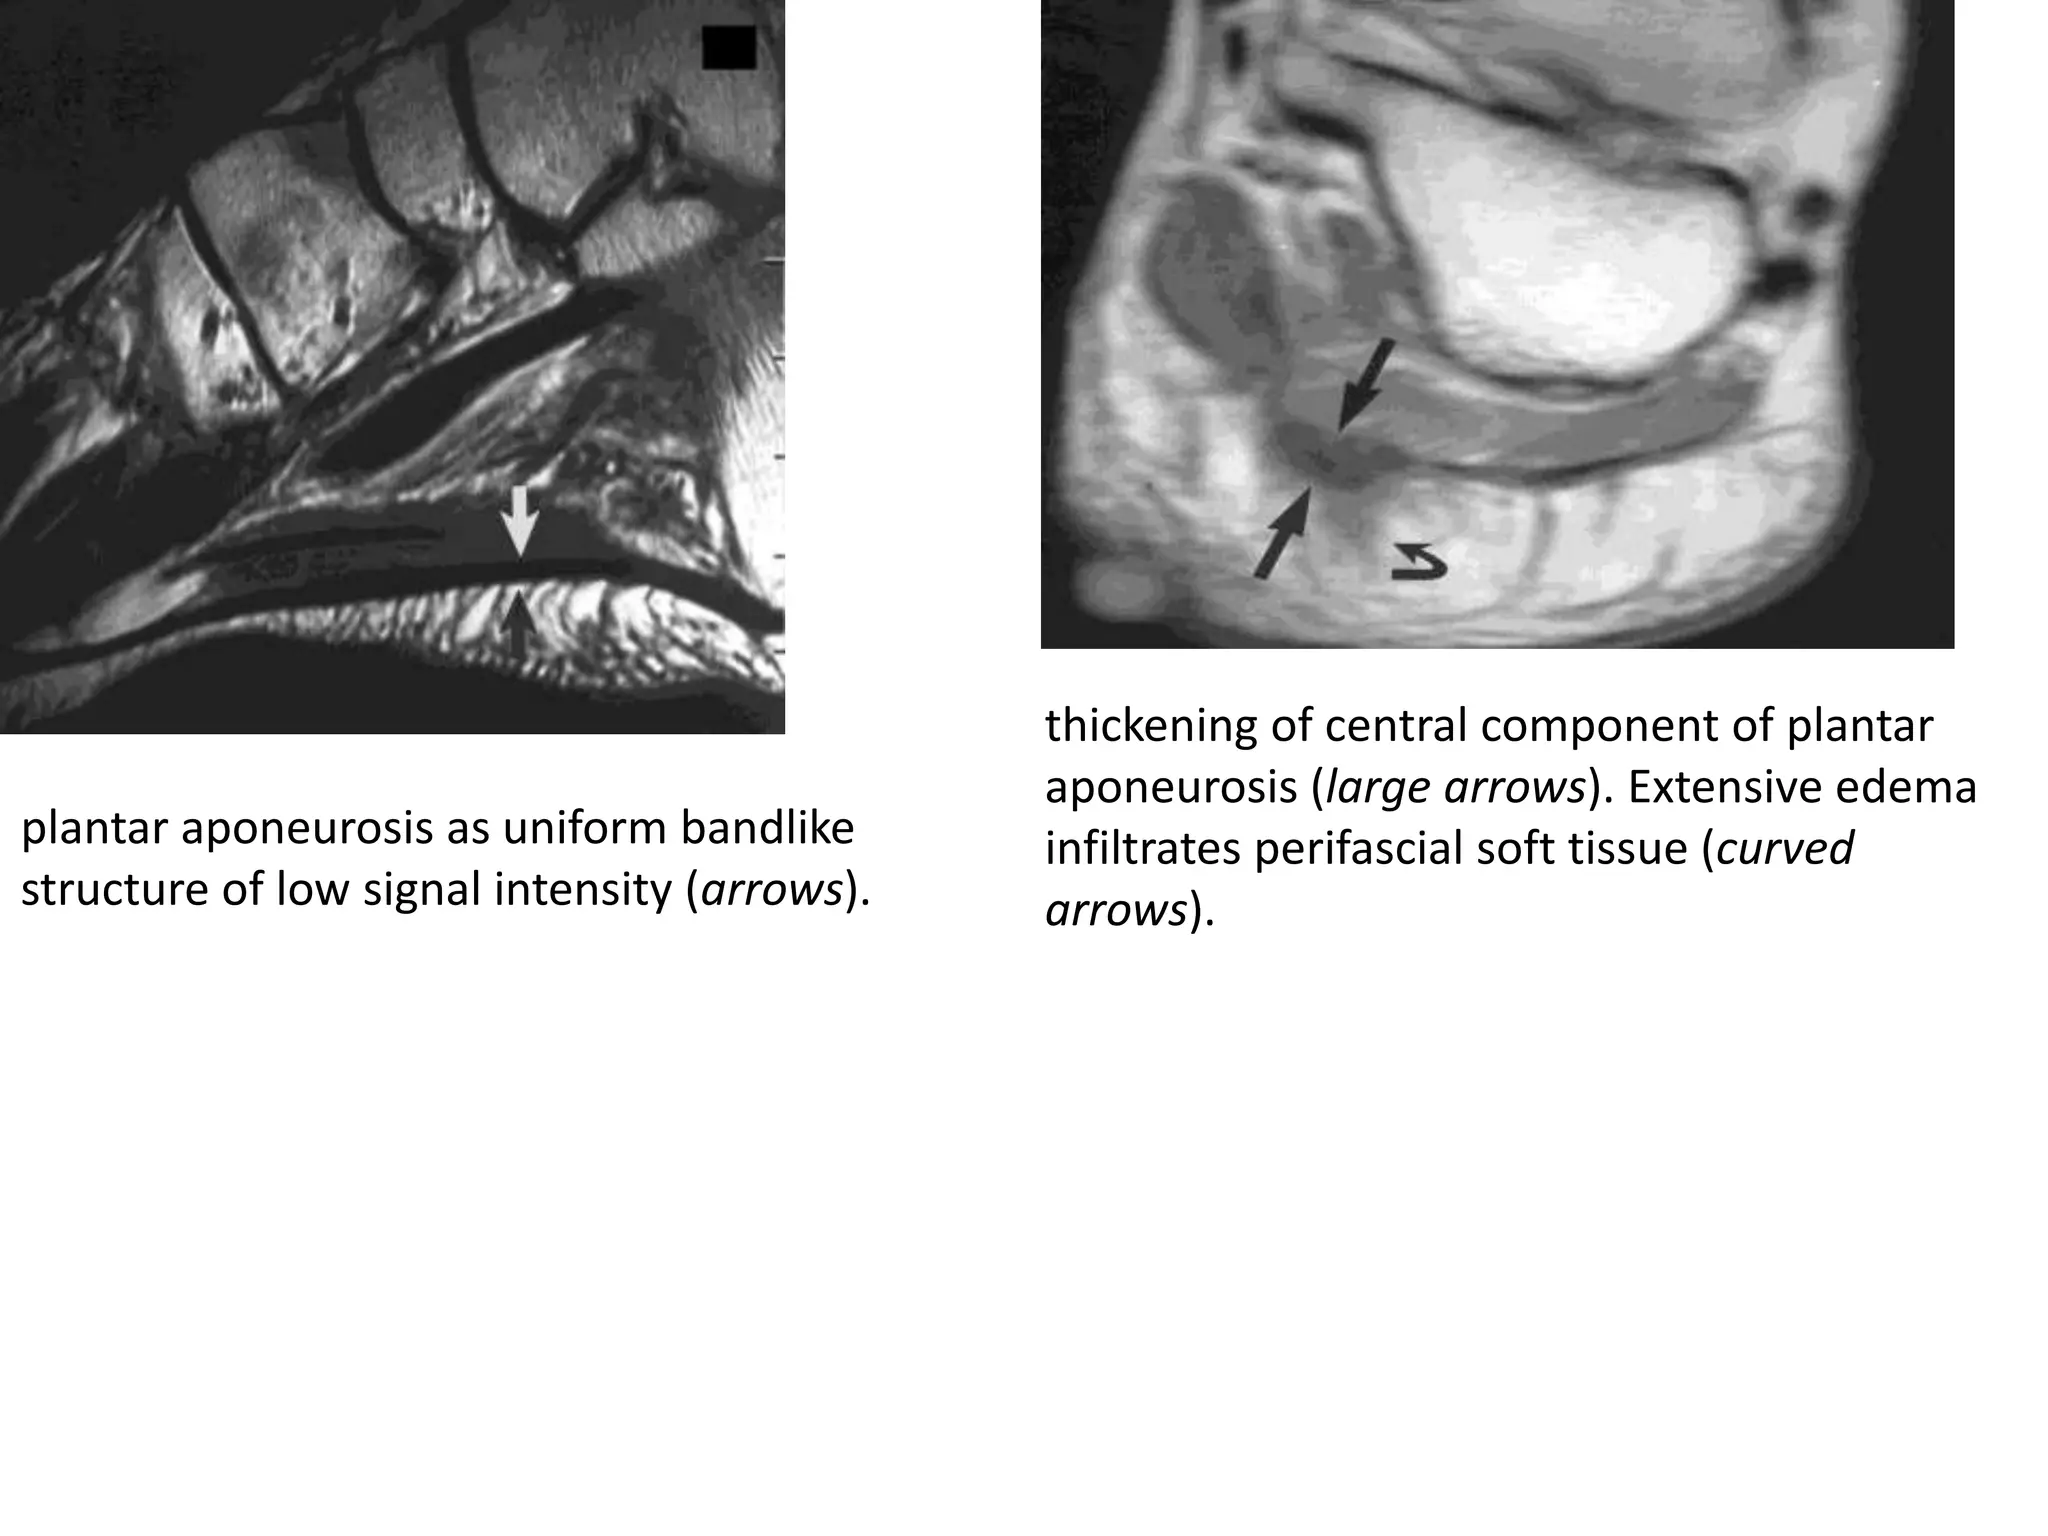

thickening of central component of plantar

plantar aponeurosis as uniform bandlike       infiltrates perifascial soft tissue (curved

structure of low signal intensity (arrows).   arrows).